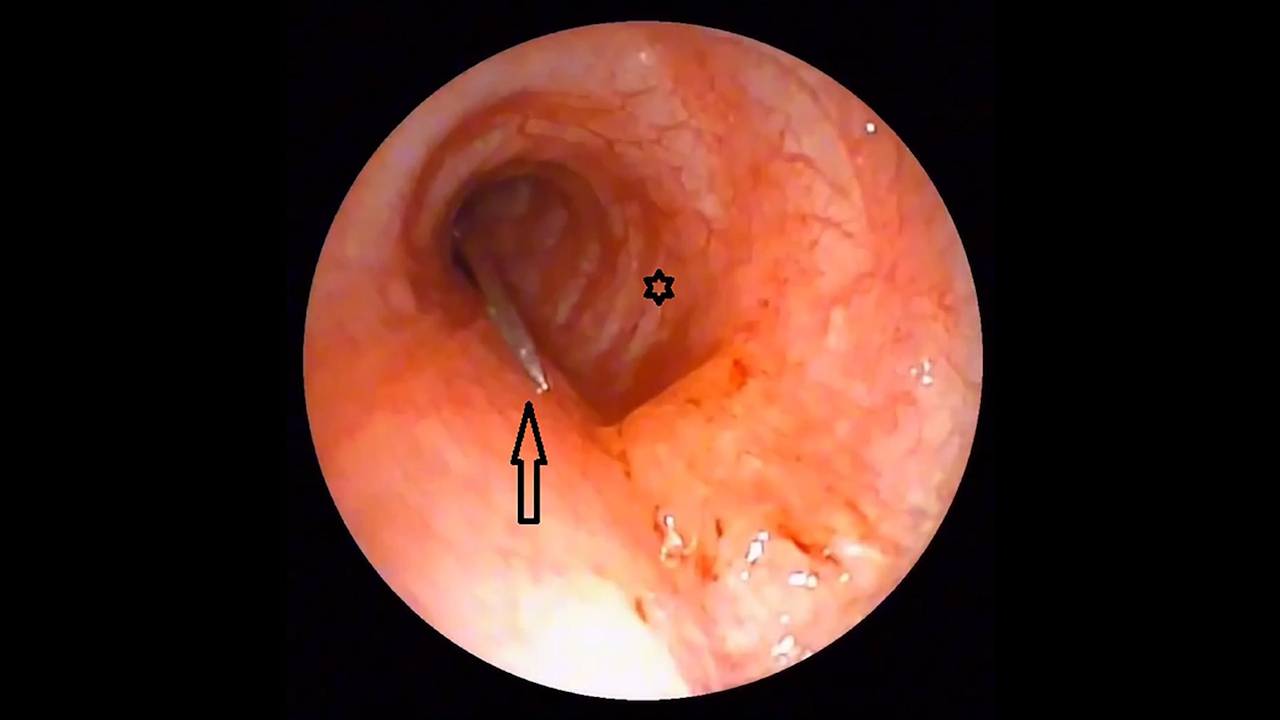

Видалення шпильки провели під загальною анестезією. Для цього в бронхи ввели гнучкі інструменти для ендоскопії зі щипцями на кінці, які зазвичай використовують для забору тканин зі шлунка. Схопивши шпильку за гострий кінець, хірурги безпечно її вивели з бронхів. Оскільки на шпильці були сліди іржі, дівчині зробили щеплення від правця, а також призначили курс антибіотиків для запобігання іншим інфекціям. Лікарі зазначають, що успіху операції посприяло використання саме гнучких інструментів, адже тверді інструменти збільшують ризик пошкодження легень у таких випадках і можуть навіть призвести до смерті пацієнта.